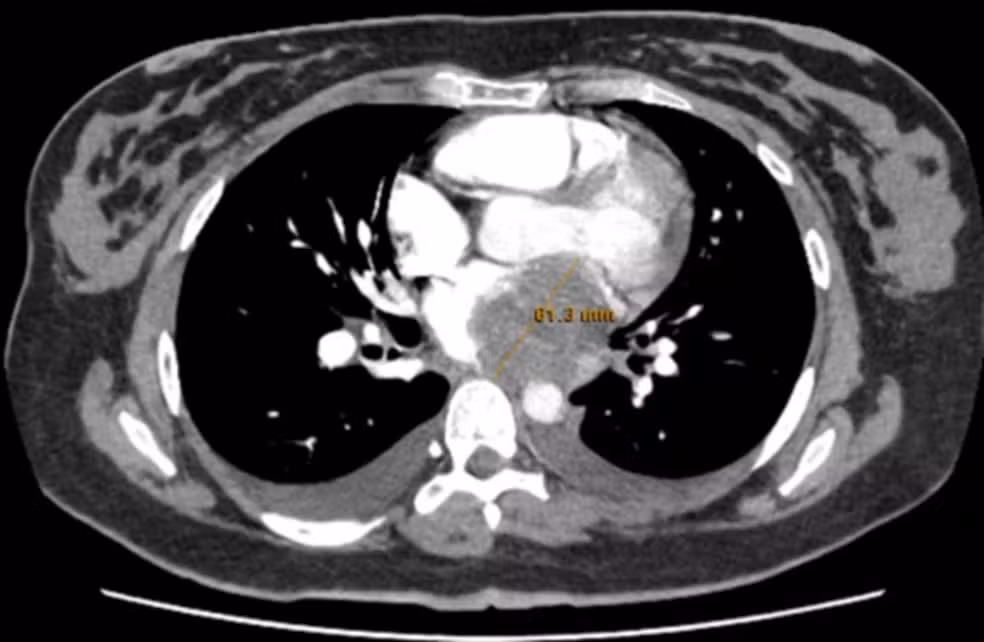

Uma mulher de 23 anos chegou ao pronto-socorro com falta de ar progressiva e palpitações havia quase três semanas. Jovem, sem doenças prévias conhecidas, ela parecia um caso típico de embolia pulmonar — hipótese reforçada por exames laboratoriais alterados. Mas a tomografia descartou o coágulo no pulmão e revelou algo inesperado: uma massa de cerca de 6 centímetros ocupando o átrio esquerdo do coração.

No caso publicado, o tumor foi identificado primeiro por tomografia e confirmado por ecocardiograma, que mostrou obstrução significativa do fluxo sanguíneo.